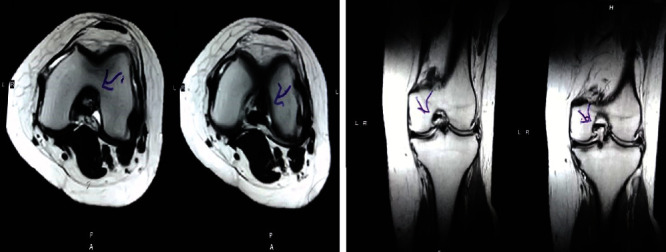

治療后一個(gè)月進(jìn)行隨訪(fǎng)。在第一次細胞治療后,患者的疼痛明顯減輕。第二次療程后,她沒(méi)有疼痛,并注意到運動(dòng)范圍有所改善。持續的物理治療也觀(guān)察到下肢肌肉力量的增加。從治療開(kāi)始(11個(gè)月前)到最后一次隨訪(fǎng)(4個(gè)月前),患者按照建議的飲食和基于運動(dòng)的方案減重了11公斤。因此,她現在整體身體健康,能夠更舒適地進(jìn)行日常生活活動(dòng)。表3顯示治療前后的MRI檢查結果。人物的圖1和的和圖2顯示半月板撕裂的治療前和治療后(1年后)圖片。觀(guān)察到損傷程度的改善圖2。

圖2:治療后MRI顯示內側和外側半月板后角的撕裂有所改善?;颊呓?jīng)歷了癥狀改善以及進(jìn)行日常生活活動(dòng)的能力增強。